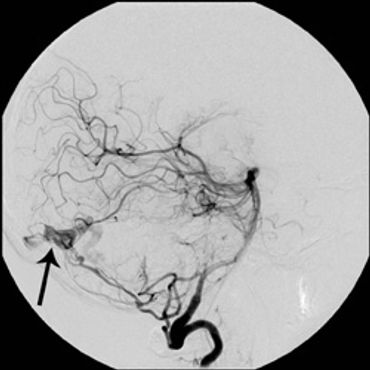

A dural arteriovenous fistula (DAVF) is an abnormal connection between arteries and veins located in the dura mater, the tough outer covering of the brain and spinal cord. These abnormal connections disrupt normal blood flow, potentially leading to various neurological symptoms.